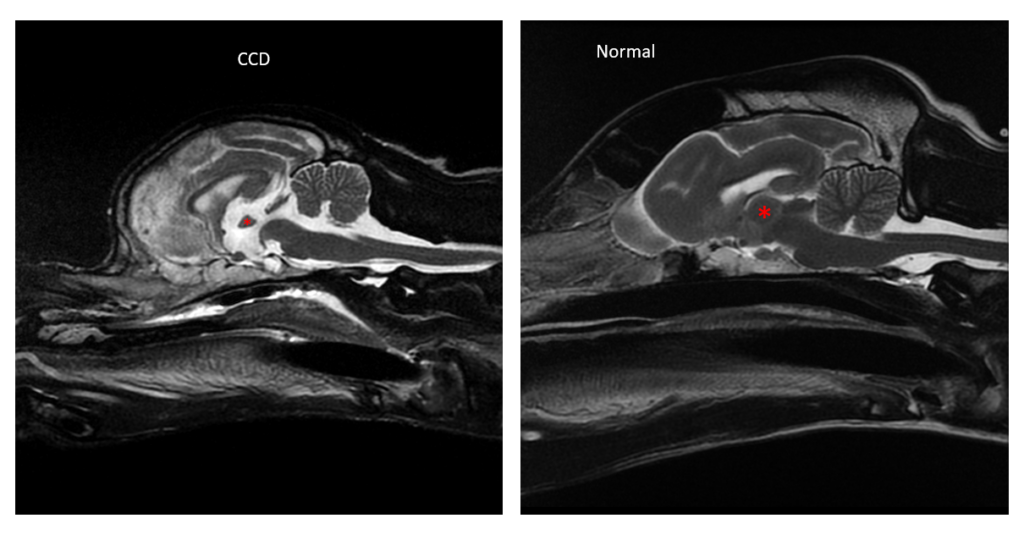

If clinical signs of dog dementia are recognized, an MRI can help with diagnosis of CCDS. Degenerative brain diseases like canine cognitive dysfunction syndrome literally cause the brain to shrink, which can be captured by an MRI. MRI also helps to exclude other conditions that could impact a dog’s health.

“Most degenerative diseases are progressive, which means the brain atrophies, or shrinks,” Bartner said.

The problem is that brain atrophy is easiest to identify on an MRI scan when cognitive decline is advanced, so once more consistent clinical signs are noticed and later than is ideal for intervention. The further the disease progresses, the less cognitive function there is to try to preserve.